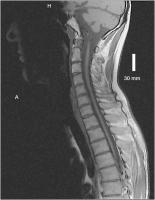

Abbildung 1: Axiale T2 des Gehirns: Ausgeprägte hyperintense Signalveränderungen im Centrum semiovale erkrankungstypisch im dorsalen Anteil.

Keywords:

Adrenomyeloneuropathie

,

Centrum semiovale

MRT

Neurologie

Signalstörung